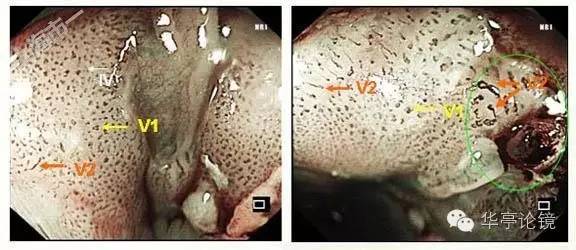

ME-NBI内镜:见多处病灶粘膜血管网异常,分支血管网缺失,局部背景着色阳性,IPCL呈IV-V1型改变为主(注:IV型: 出现扩张、迂曲、管径粗细不均或形态不规则改变中的2种或3种;V型:同时出现扩张、迂曲、管径粗细不均和形态不规则四种改变),局部见V2型改变(注:Ⅴ2型:在Ⅴ1型病变的基础上出现血管延长,原血管袢结构尚完整)。预测病变深度为m1(上皮层)为主,见下图。本文IPCL分型均按井上分型方法。